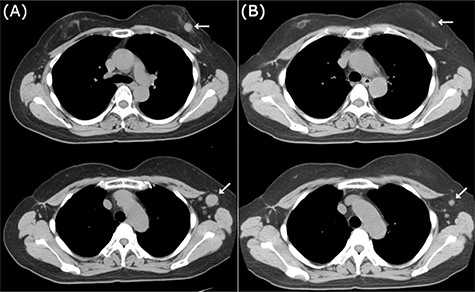

CT images of right breast tumor before and after treatment. (A) Chest CT displaying nodules in the right breast (top, arrowhead) and lymph node swelling in the right axilla (bottom, arrowhead); (B) after administration of NAC, the primary tumor (top, arrowhead) and axillary lymph nodes (bottom, arrowhead) displayed a clear reduction in size.

CT images of left breast tumor before and after treatment. (A) Chest CT displaying a nodule in the left breast (top, arrowhead) and lymph node swelling in the left axilla (bottom, arrowhead); (B) Tumors in both the left breast (top, arrowhead, arrowhead) and the axillary lymph node (bottom, arrowhead, arrowhead) shrank after carboplatin and paclitaxel administration.